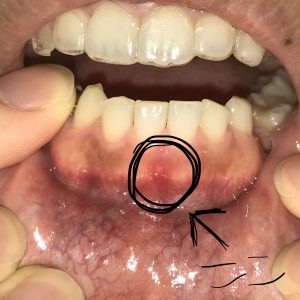

ニコチン性口内炎 舌 (461 無料写真)

ニコチン性口内炎 舌